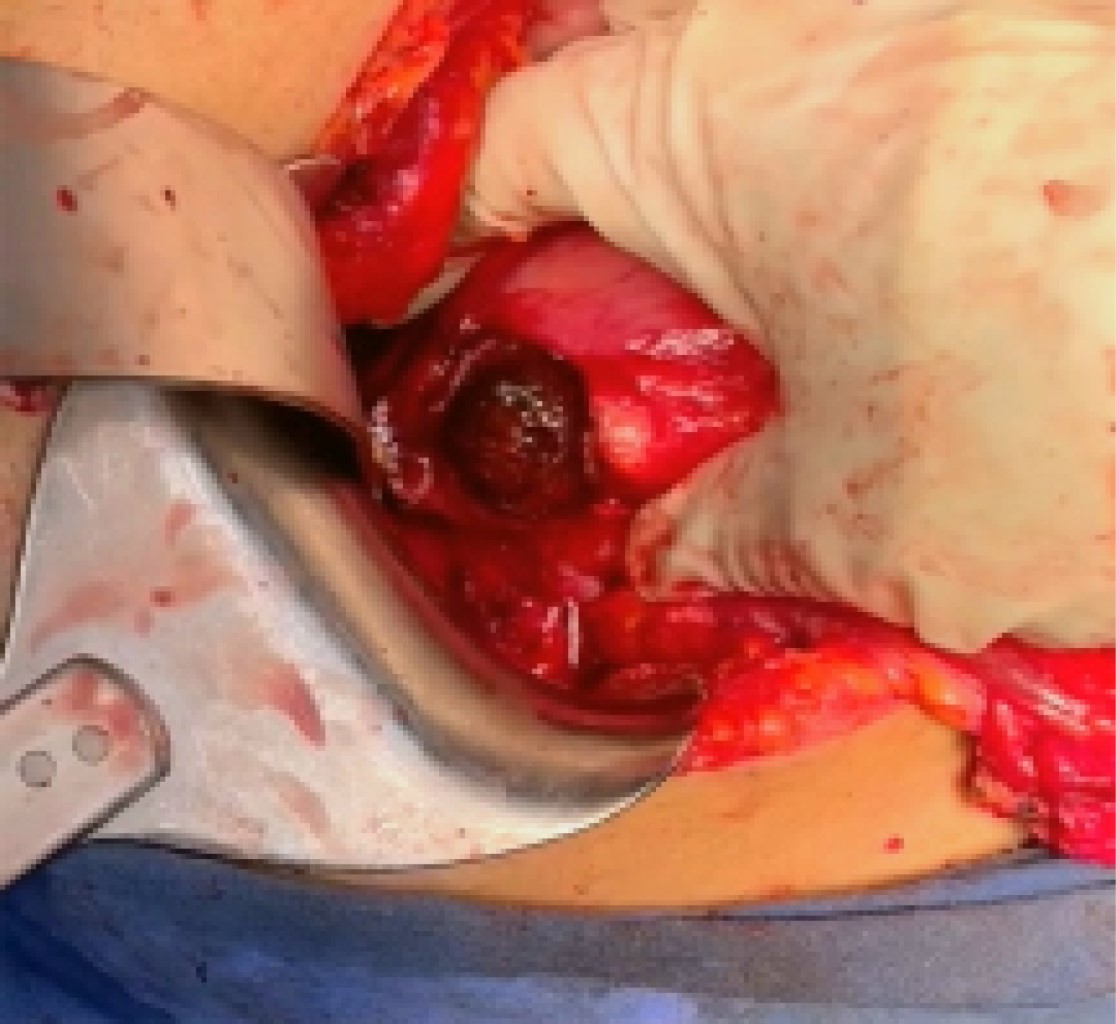

Due to imaging findings, a cholecystogastric fistula was suspected, and the patient was scheduled for open cholecystectomy. Other findings were important adhesive process, a scleroatrophic gallbladder, and a cholecystogastric fistula are evidenced. We proceeded to perform gastrorrhaphy and extraction of a 2 × 3 cm litho with primary closure of the fistula. It was decided to place a nasojejunal tube to keep the pylorus bypassed. A cholecystostomy tube was placed (Figure 3).

Figure 3